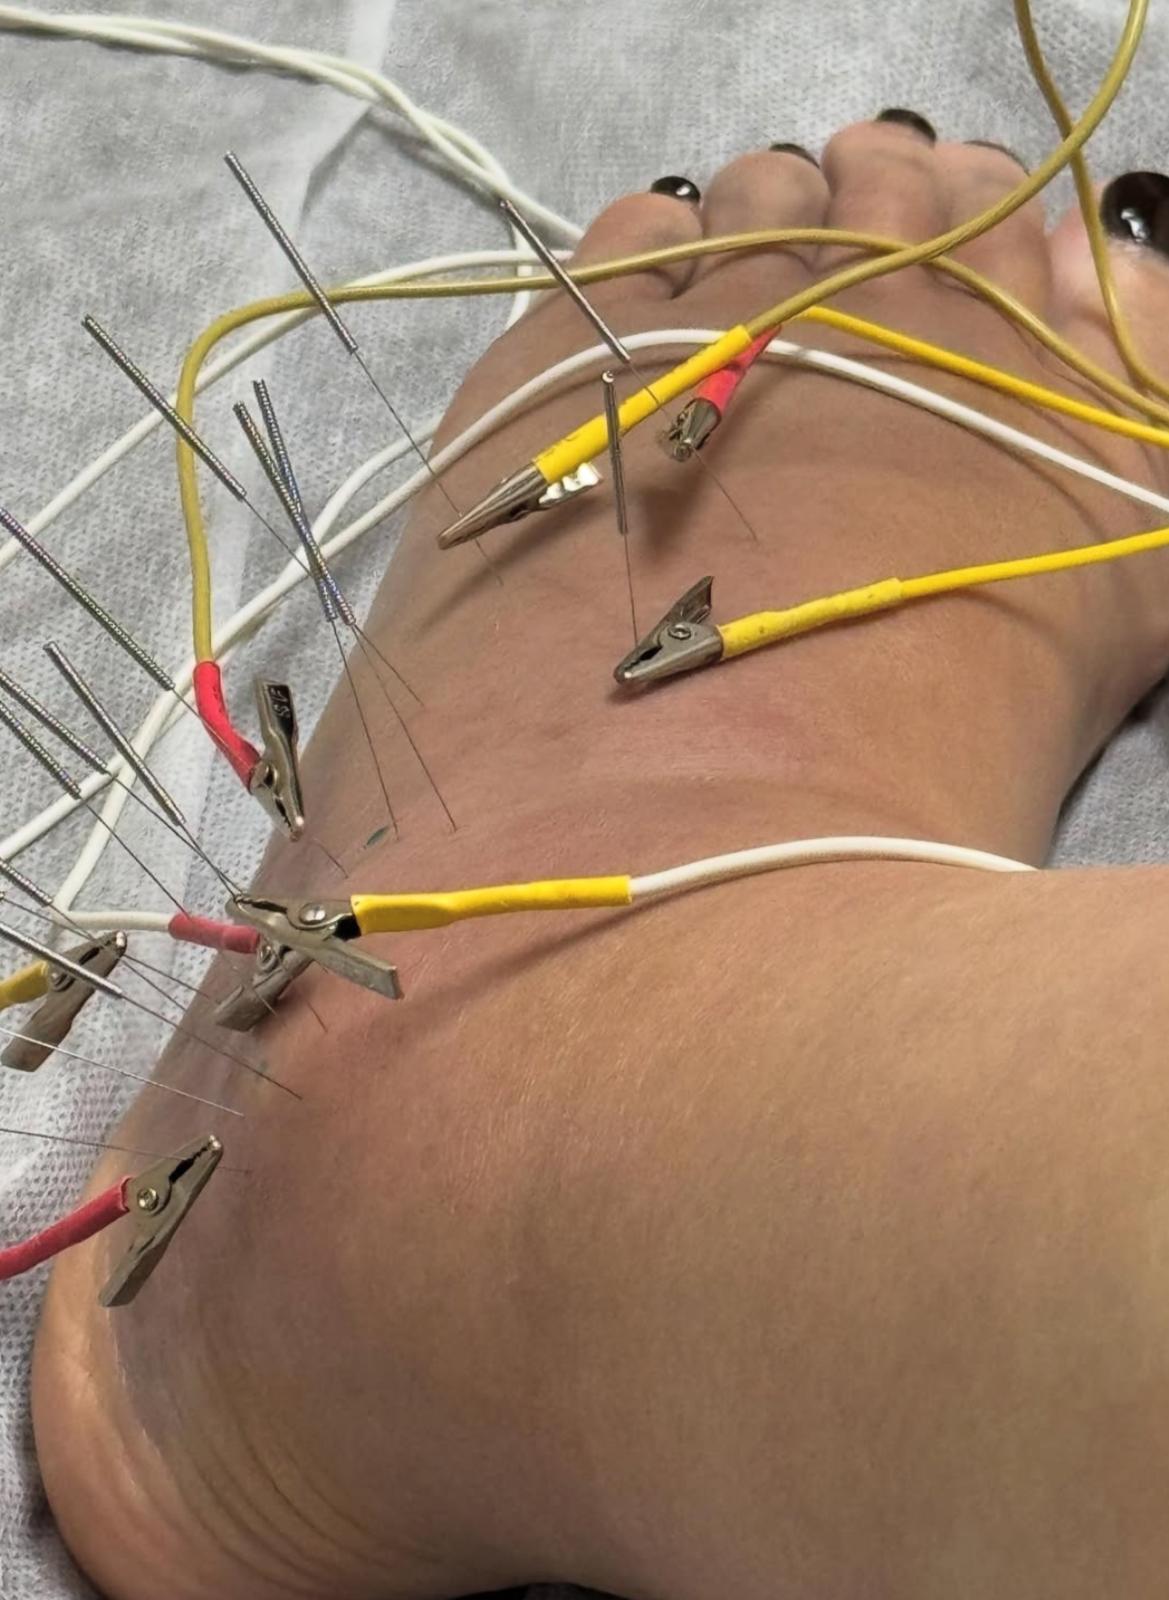

余安安在上年播出的劇集《家族榮耀之繼承者》演戴綺婷一角,獲得觀眾大讚演技出色,最近她甚少參與幕前演出。余安安前日(8日)在社交網自爆兩星期前人生第一次拗柴,後來情況嚴重到骨裂,需要接受中西合璧治療。另外她還上載一系列腳傷情況的照片,她需要靠雙手撐住枴杖行路,而左腳要用護具固定。

余安安發文指拗柴原本以為拗柴的情況並不是太嚴重,所以當晚忍痛陪伴孫仔去看燈飾。她續說:「再過多兩日又覺得唔多妥去照埋X-Ray,原來骨裂咗,不幸中之大幸係冇移位,要買對超貴嘅boot着,慶幸係左腳,右腳最近仲可以揸到車。」